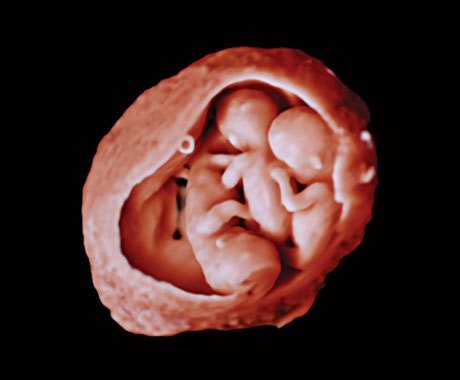

Neste vídeo, o Dr. Michael Ruma apresenta o transdutor 3D de ultrassons V9-2 da Philips. O V9-2 é o primeiro transdutor mecânico 3D PureWave de ultrassons da Philips para obstetrícia/ginecologia que oferece uma excelente qualidade de imagem e um design ergonómico avançado. O V9-2 é extraordinário em imagiologia 2D, 3D, 4D para exames obstétricos do 1.º, 2.º e 3.º trimestres.